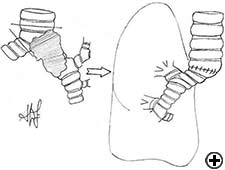

Carinal resection is a complex and aggressive procedure for the treatment of bronchial tumors involving the carina, the tracheo-bronchial angle or the distal portion of the trachea (Figure 1). The airway is reconstructed by anastomosis of the opposite main bronchus (tracheal sleeve pneumonectomy) or both bronchi (isolated carinal resection) to the lower trachea (Figure 2). The most common indication for a sleeve pneumonectomy is a tumor involving the origin of right main bronchus or extending into the lower trachea. Left sleeve pneumonectomy is rarely indicated since the left main bronchus is considerably longer than the right one and, in the case of carinal infiltration, tumor usually invades the structures in the subaortic space as well, which frequently implies inoperability. An isolated carinal resection and reconstruction may be applicable for centrally located, low grade and small tumors of the carina not extending so far to the main bronchi. Carinal resection represents a challenge for thoracic surgeons and anesthesiologists related to demanding intraoperative airway management, the technique of anatomic reconstruction and the risk of significant postoperative morbidity, mortality and poor long-term outcome [11].

In isolated carinal resection and reconstruction, applicable for centrally located, low grade and small tumors (Video 8), the right and left main bronchi can be medially sutured to create a new carina, that is subsequently anastomosed to the distal trachea (Figure 2C and Video 9). A less common technique provides the resection of the carina followed by an end-to-end anastomosis between the left main bronchus and the trachea, followed by anastomosis of the right main bronchus to the lateral, cartilaginous wall of the trachea, paying attention to stay at least 2 cm above the first anastomosis (Figure 6). When more advanced tracheal involvement is present, two alternative techniques may be used to avoid excessive tension: an end-to-end anastomosis between the right main bronchus and the trachea, followed by anastomosis of the left main bronchus to the lateral, cartilaginous wall of the bronchus intermedius or an end-to-end anastomosis between the left main bronchus and the trachea, followed by anastomosis of the right main bronchus to the lateral, cartilaginous wall of the left main bronchus (Figure 7). In all of cases a wide hilar release is mandatory to reduce tension on the anastomoses.

Tracheal sleeve lobectomy is a challenging operation usually required for management of neoplasms involving the trachea or the carina and the proximal right main bronchus extending to the origin of the right upper bronchus (Figure 8). In cases of contraindication for sleeve pneumonectomy or in case of low-grade neoplasm, the carina, right main bronchus, and right upper lobe may be removed. The reconstruction consists of an end-to-end anastomosis of the left main bronchus to the trachea, and creation of a secondary end-to-side anastomosis of the bronchus intermedius either to the trachea (Figure 9) or more frequently to the left main bronchus (Figure 10), because elevating the bronchus intermedius to the side of the trachea often creates excessive tension, with high risk of fistula or stenosis.